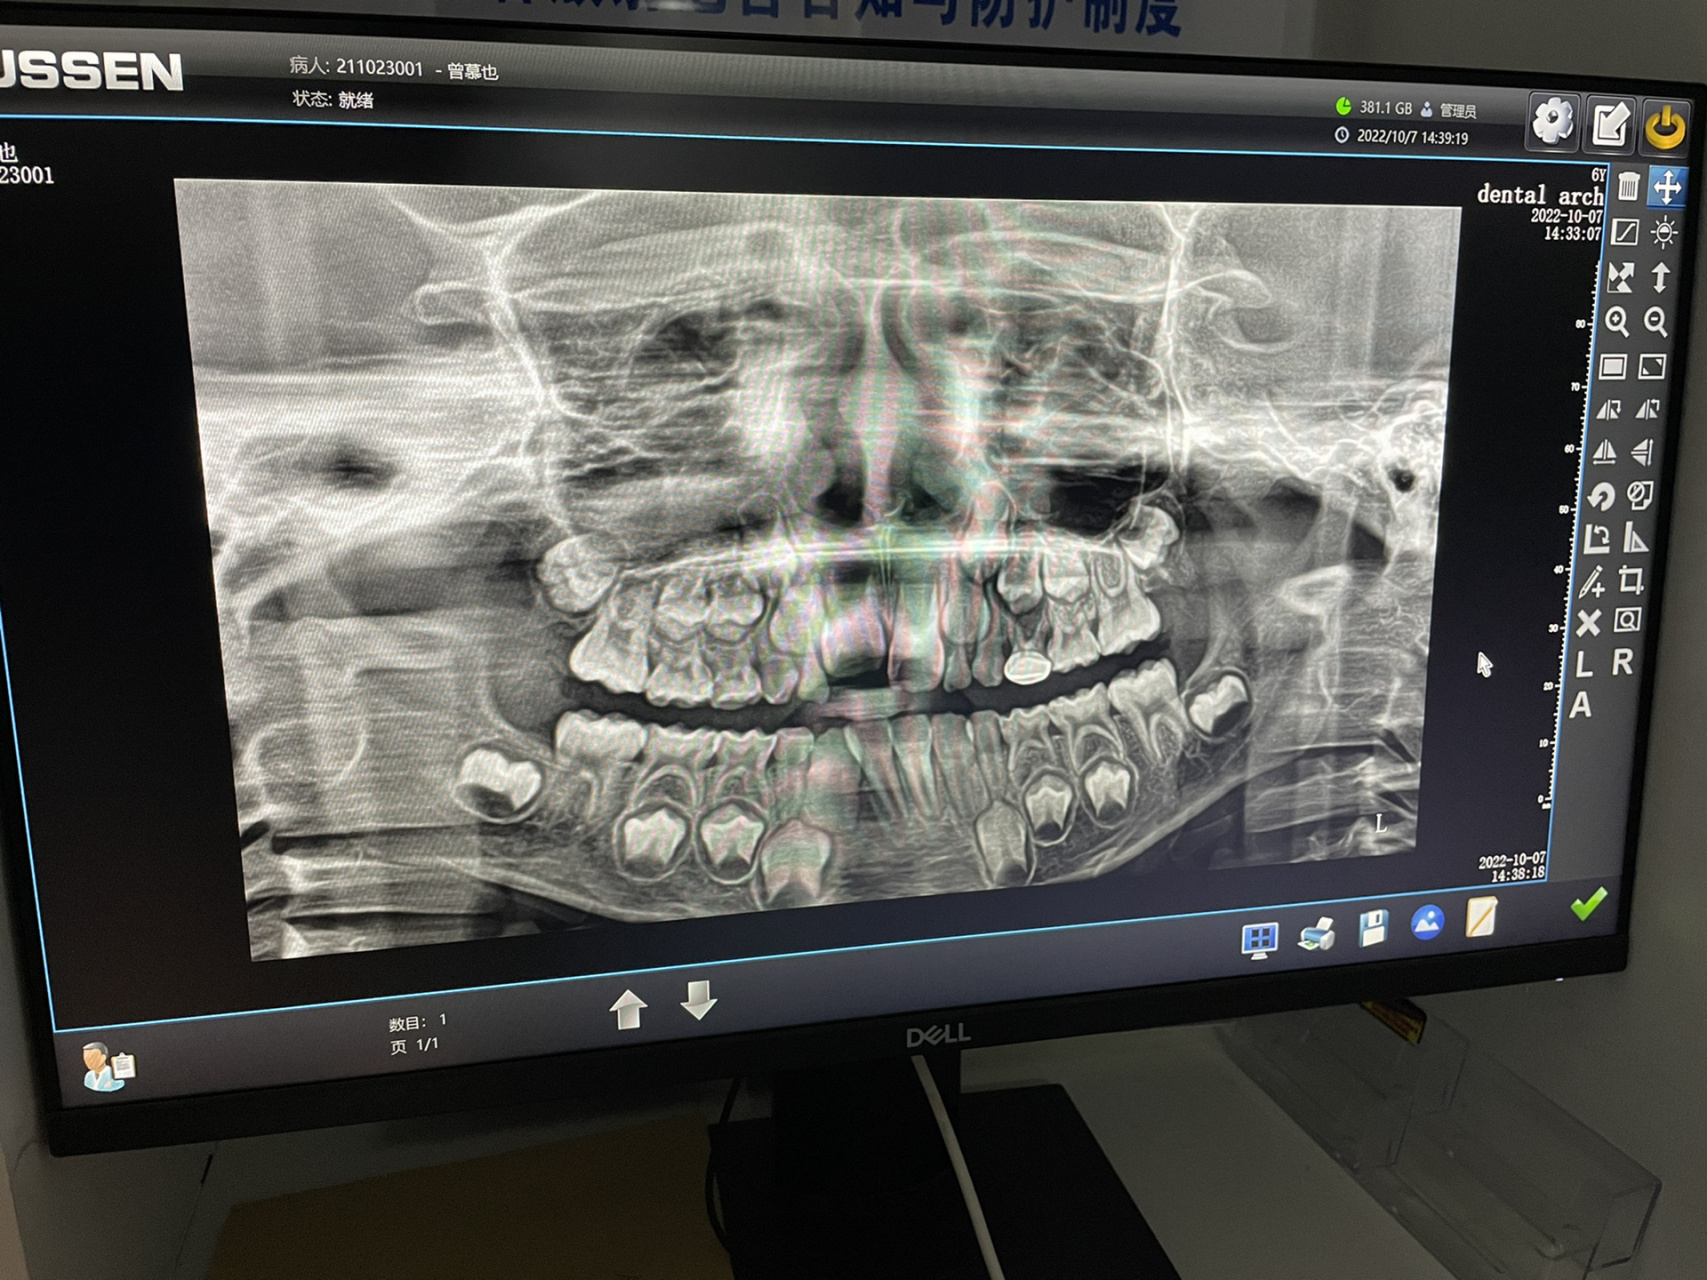

7周岁小朋友的牙片 我侄女刚拍的牙片,好多牙齿07

图片尺寸1920x2560